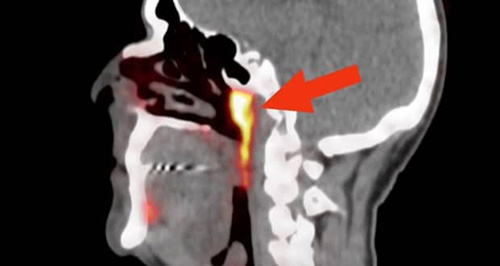

پژوهشگران هلندی زمانی که مشغول بررسی وضعیت بیماران مبتلا به سرطان پروستات بودند، مقداری گلوکوز رادیواکتیو را به بدن این افراد تزریق کردند. چنین روشی در کنار استفاده از اسکن PSMA PET/CT میتواند محل دقیق تومورها در بدن انسان را مشخص کند؛ اما در کمال تعجب، ماده مورد نظر در قسمت دیگری از بدن و جایی که کسی انتظار آن را نداشت، ظاهر شد. دانشمندان مشاهده کردند که گلوکز رادیواکتیو به کار رفته پشت قسمت بالایی حلق را نورانی کرده بود.

قسمتهای نارنجی رنگ عکس بالا سایر غدههای بزاقی سر هستند و بخشی که با فلشهای آبی نشان داده شده، همان عضو جدید و مرموز بدن است. وتر ووگل (Wouter Vogel) از موسسه سرطان هلند میگوید که بدن انسان شامل سه جفت غده بزاقی بزرگ میشود، اما هیچکدام از این جفتها در پشت قسمت بالایی حلق قرار ندارند.